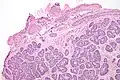

Micrograph of a Sertoli cell nodule. H&E stain.

A Sertoli cell nodule is a benign proliferation of Sertoli cells that arises in association with cryptorchidism (undescended testis).[1] They are not composed of a clonal cell population, i.e. neoplastic; thus, technically, they should not be called an adenoma.[2]

Sertoli cell nodules are unencapsulated nodules that consist of:[2][3][4]

1. cells arranged in well-formed tubules (that vaguely resemble immature Sertoli cells), with

2. bland hyperchromatic oval/round nuclei that are stratified, and

3. may contain eosinophilic (hyaline) blob in lumen (centre).